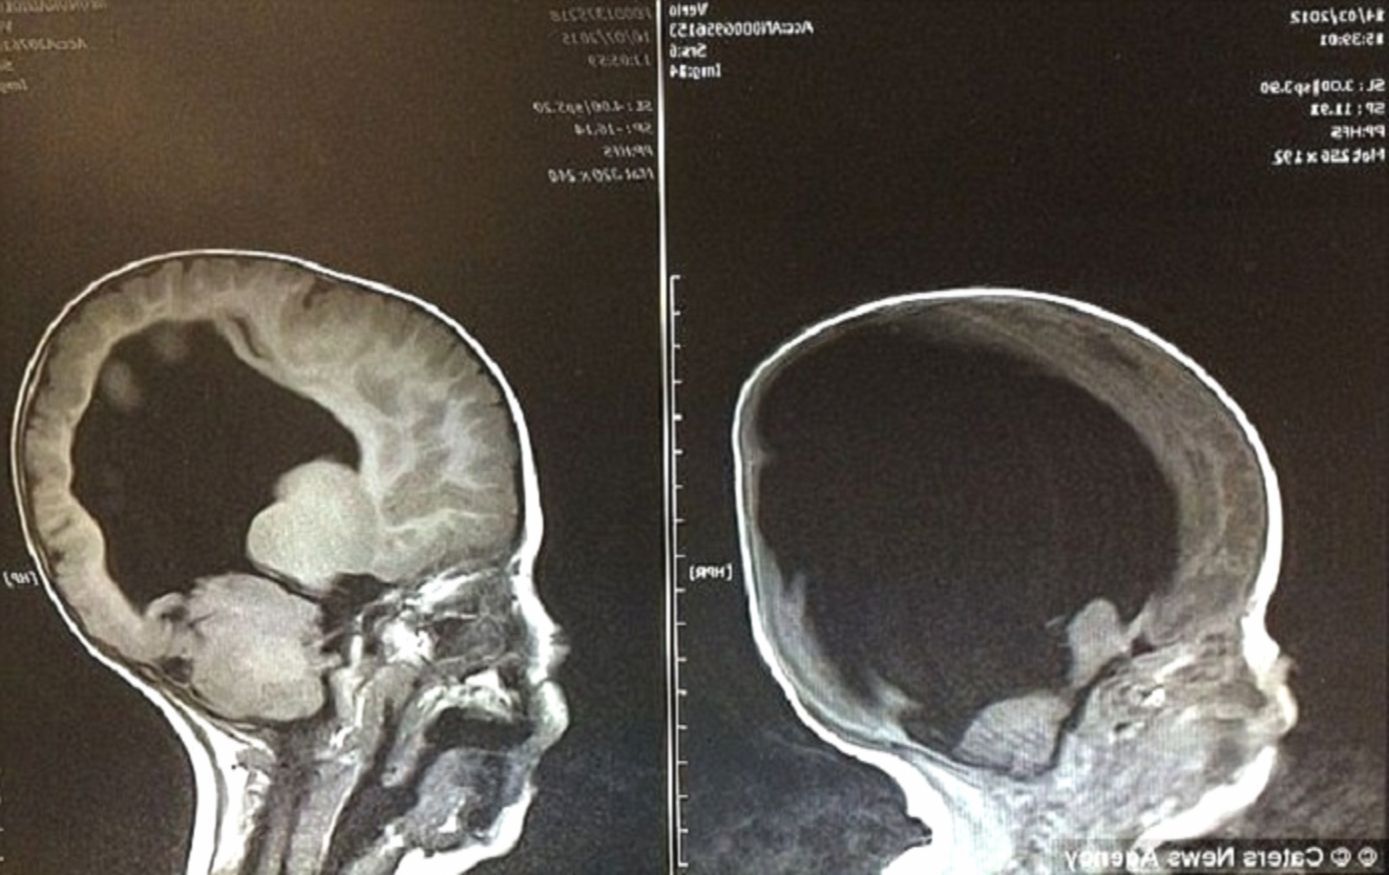

Когда Шелли и Роб Уолл из британского графства Камбрия услышали вердикт врачей, мир вокруг них должен был рухнуть. На снимке УЗИ вместо развивающегося мозга их будущего сына зияла пустота, заполненная жидкостью.

Медики были суровы и единодушны: у ребенка функционирует лишь два процента мозга, он не выживет после рождения, а если и случится «невозможное», он навсегда останется «овощем», неспособным ни чувствовать, ни осознавать реальность.

Первым шагом к спасению стала сложнейшая операция. Нейрохирурги установили в голову малыша шунт — специальную трубку для отвода лишней жидкости. И тут произошло то, что наука до сих пор называет медицинской загадкой. Мозг Ноя не был «отсутствующим» в буквальном смысле — ткани были экстремально сдавлены скопившейся жидкостью.

Как только давление спало, серое вещество начало буквально расправляться и расти, словно цветок, получивший долгожданную воду. К трем годам объем мозга Ноя достиг невероятных восьмидесяти процентов от нормы. Мальчик, которому прочили растительное существование, заговорил.